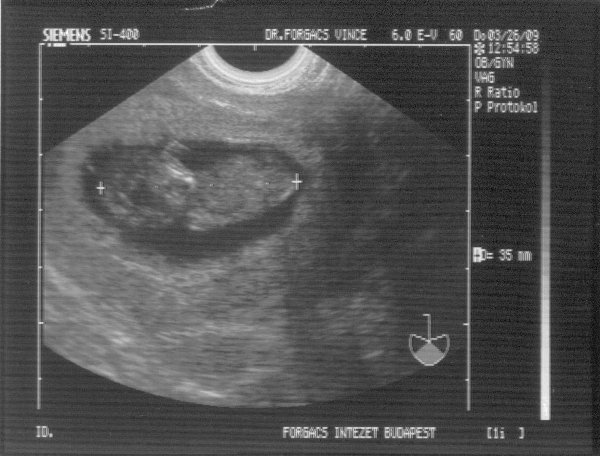

A baba miatt meg ne aggódj! Hidd el, nem lesz semmi baj. Azért a nemét megmutathatta volna. Már olyan kivi vagyok.

És még szebb a babád! Annyira jó érzés lehet ezeket a képeket nézegetni.